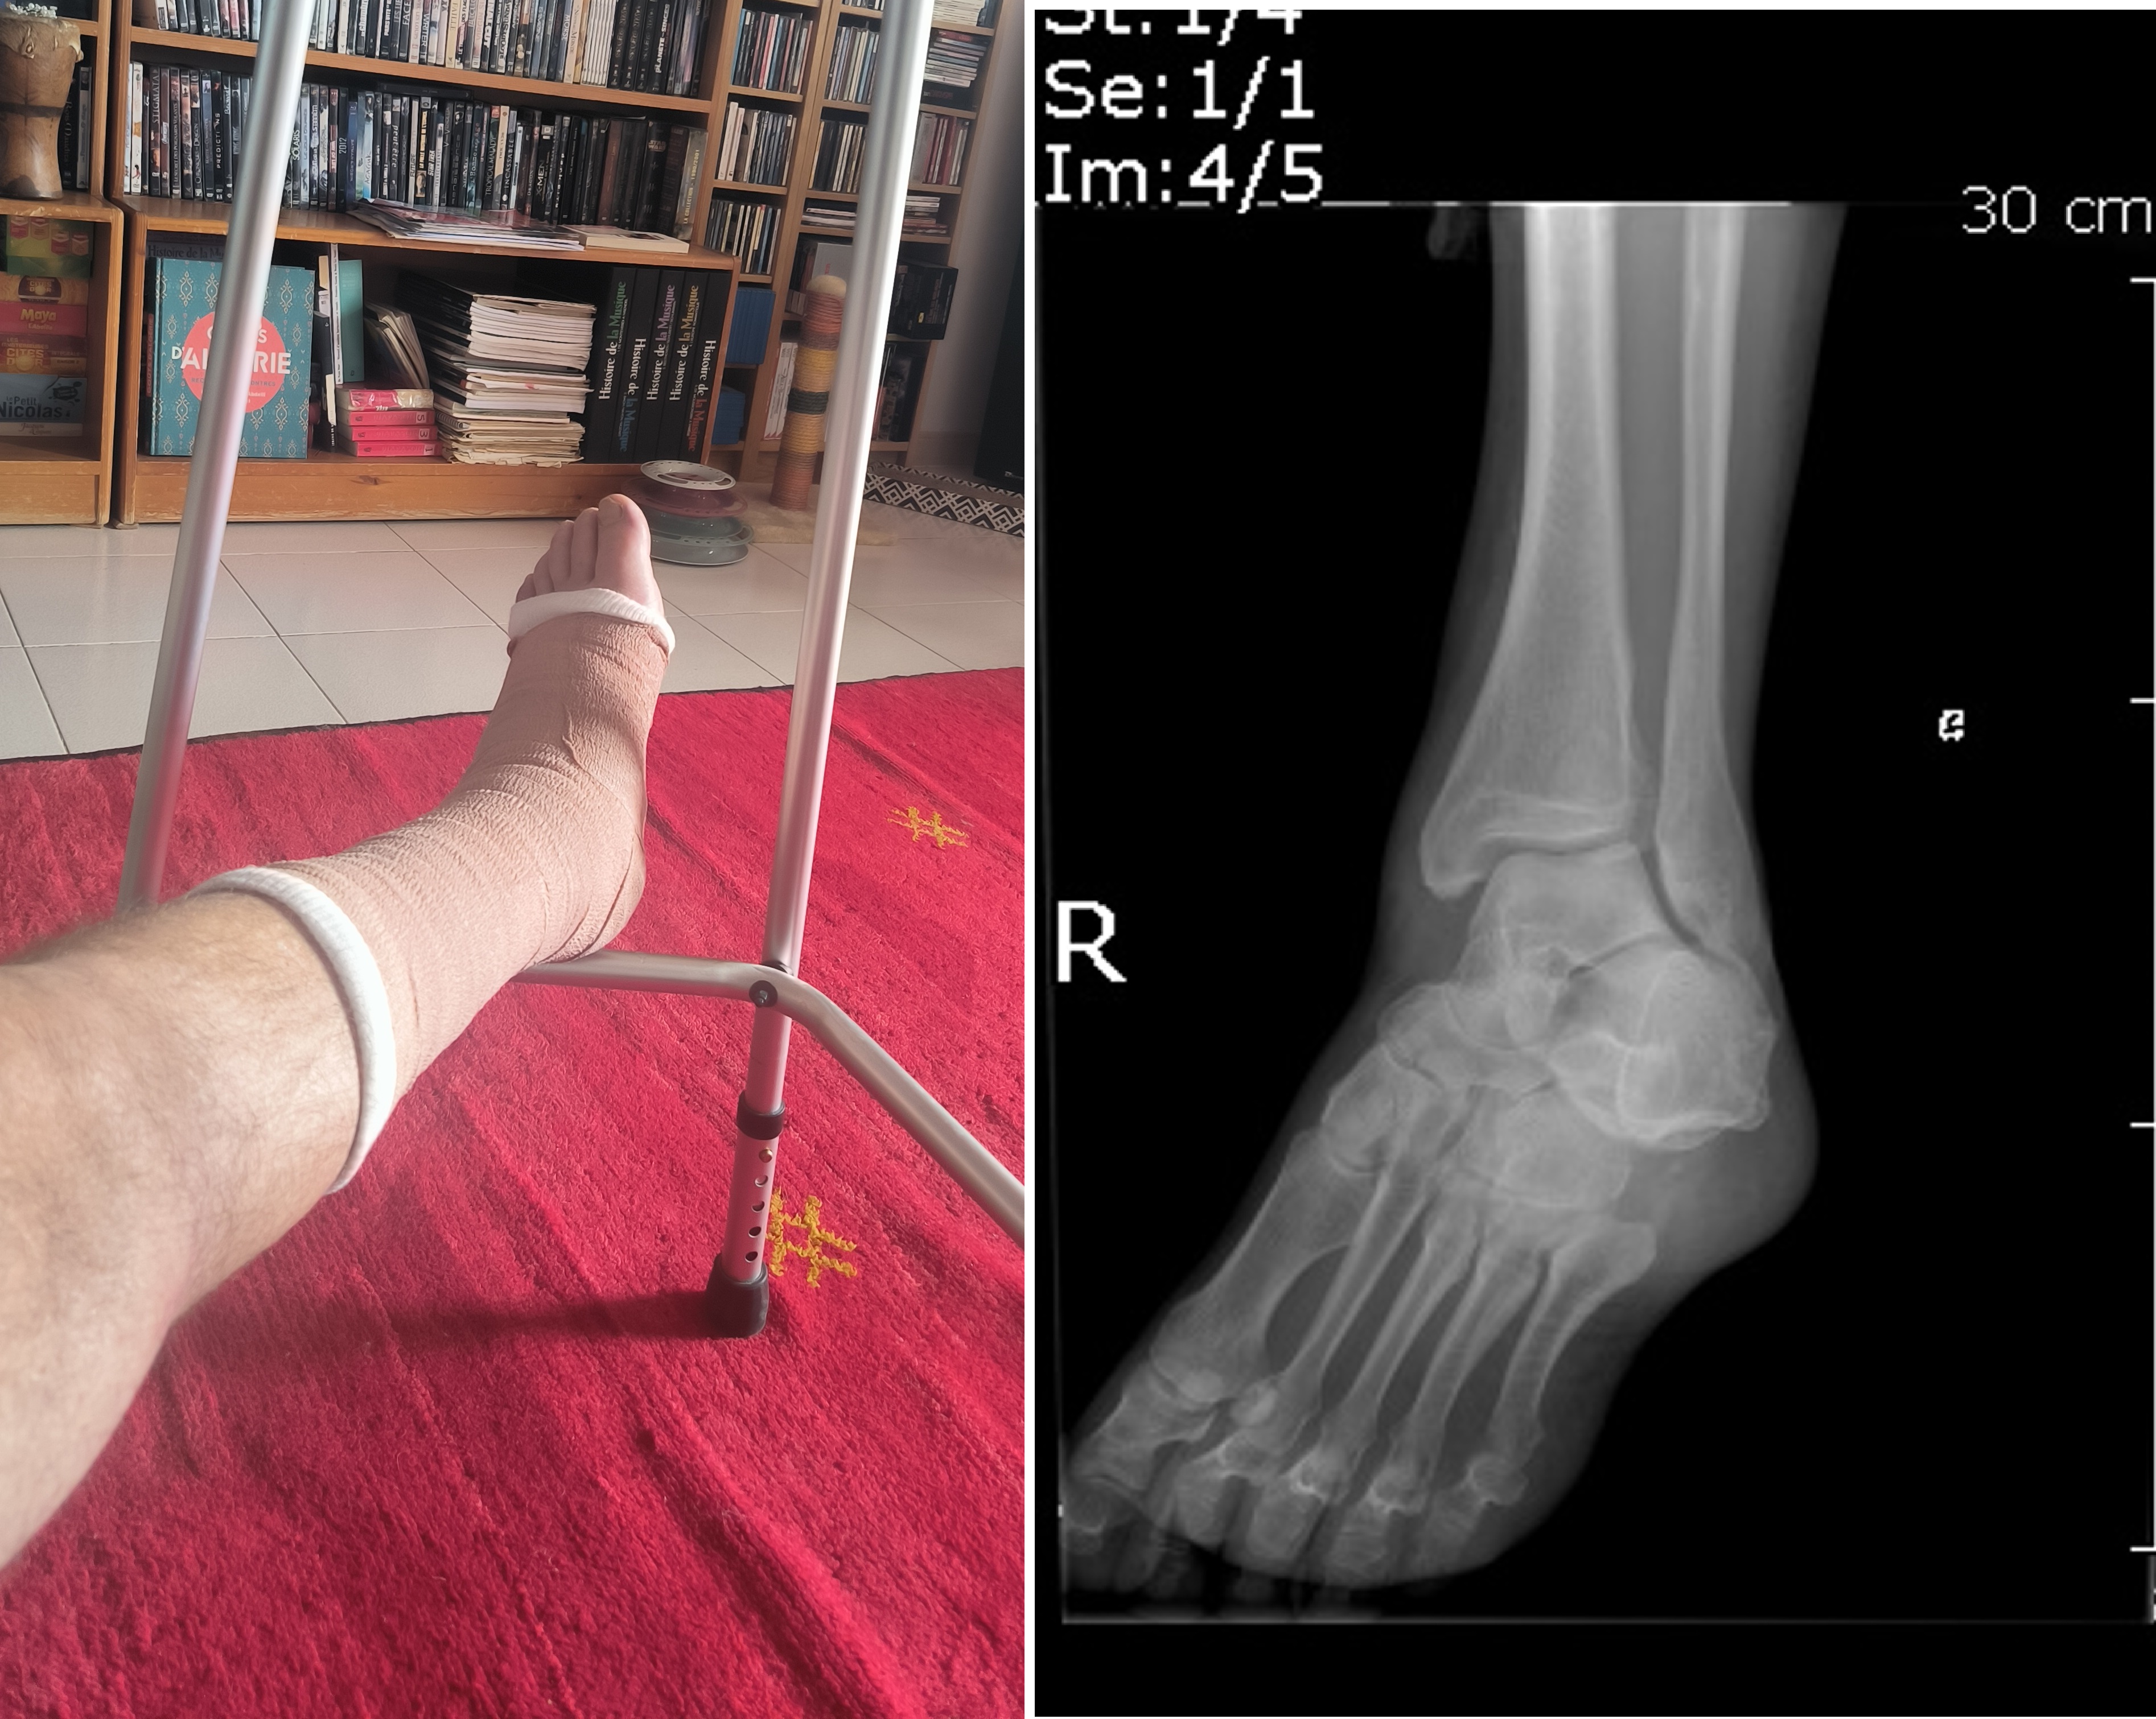

Première semaine avec un pied plâtré et les galères de mobilité qui vont avec… tout a commencé par une bête chute de vélo… à l’arrêt !

C'est en sortant de la mairie en vélo, voulant aller chez Valérie Talbi pour l'aider à emporter un frigo à la fête de quartier, que j'ai eu l'idée d'emprunter la rampe rejoignant le parking plutôt que de prendre la piste cyclable sur l'avenue Marcel Houel… passage étroit, avec du mobilier urbain… je décide de poser le pied à terre, mais il se dérobe et je tombe… pas de douleur, je vais pour me (…)